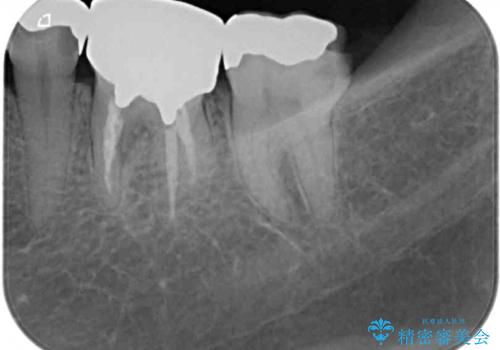

- 銀歯の奥が欠けてしまったとのことで来院された患者様です。

大きな銀歯が装着されており、その下からむし歯が広がっている状態でした。

特に症状はなく、神経組織も健全な状態であったため、むし歯を全て取り切った後にフルジルコニアクラウンにて補綴することとしました。

銀歯などを使用する保険診療は、歯との境界の適合が悪く、むし歯の再発リスクが高いため、長期的な観点から使用は推奨されません。